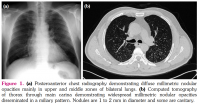

At the end of four years, chest radiography demonstrated diffuse millimetric nodular opacities mainly in upper and middle zones of bilateral lungs (Figure 1a). Computed tomography (CT) of thorax revealed widespread millimetric nodular opacities disseminated in a miliary pattern on bilateral lungs in the absence of hilar or mediastinal lymphadenopathy. The nodules were 1 to 2 mm in diameter and some of them were cavitary (Figure 1b). The patient was free of any symptom and routine laboratory analysis was normal. Pulmonary function tests were within normal limits. A written informed consent was obtained from the patient.